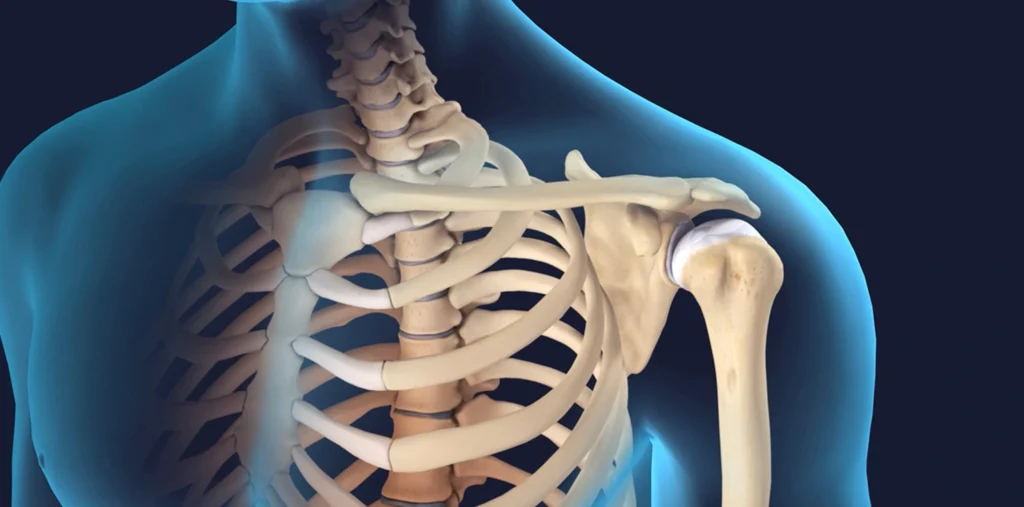

Shoulder arthroplasty involves the removal of damaged parts of the shoulder joint and replacing them with prosthetic components. The goal of the surgery is to alleviate pain, improve the range of motion, and restore shoulder function. There are several types of shoulder replacement surgeries, including:

Total Shoulder Arthroplasty (TSA): In this procedure, both the ball (humeral head) and the socket (glenoid) of the shoulder joint are replaced with artificial components.

Reverse Shoulder Arthroplasty (RSA): This procedure is typically recommended for patients with rotator cuff arthritis or severe shoulder joint damage. It involves reversing the normal anatomy of the shoulder, placing the ball on the shoulder blade and the socket on the arm bone to restore function.

Partial Shoulder Arthroplasty: This option involves replacing only the ball of the shoulder joint while preserving the natural socket. This type of surgery is typically used for patients with limited damage to the joint, such as those with fractures or isolated damage to the humeral head.

Total Shoulder Arthroplasty (TSA): This is the most common type of shoulder replacement surgery, in which both the humeral head and glenoid (shoulder socket) are replaced with prosthetic components. It is usually performed on patients with shoulder arthritis or joint degeneration.

Reverse Shoulder Arthroplasty (RSA): This procedure is used for patients with severe arthritis and a damaged rotator cuff. In reverse shoulder arthroplasty, the normal anatomy of the shoulder joint is reversed, with the ball placed on the shoulder blade and the socket on the arm bone. This surgery is highly effective in restoring shoulder function in cases of rotator cuff dysfunction.

Partial Shoulder Arthroplasty: This surgery is typically recommended for patients with isolated damage to the humeral head, such as in cases of fractures. The damaged humeral head is replaced with a prosthetic ball while the natural socket is preserved.

Surgical Procedure: The surgeon will make an incision to access the shoulder joint. The damaged portions of the shoulder, including the humeral head and glenoid, will be removed and replaced with prosthetic components. In the case of reverse shoulder arthroplasty, the normal anatomy of the shoulder is reversed to help restore function.